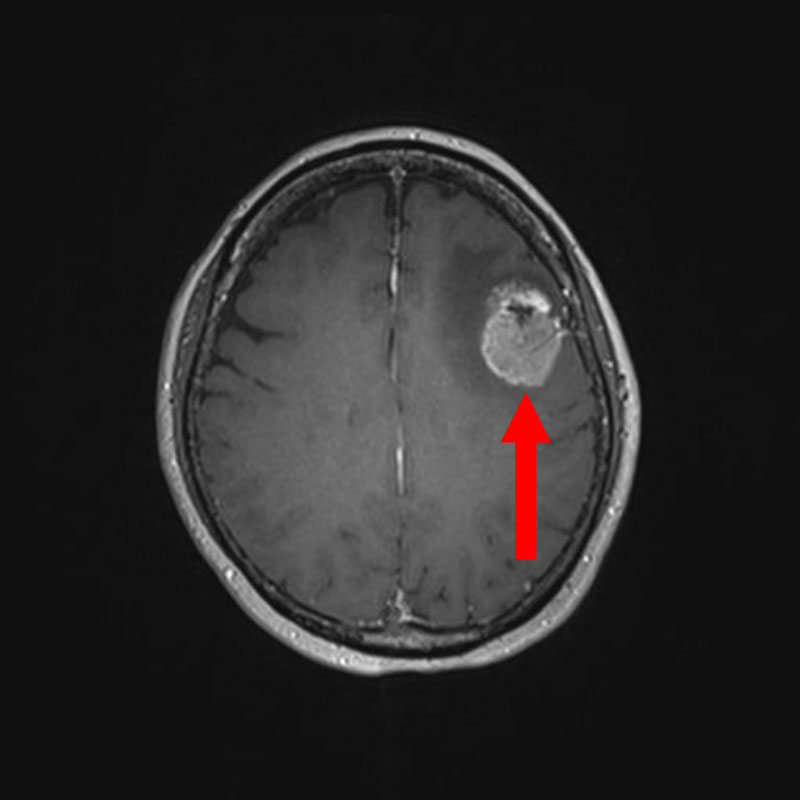

手術前1

手術前2